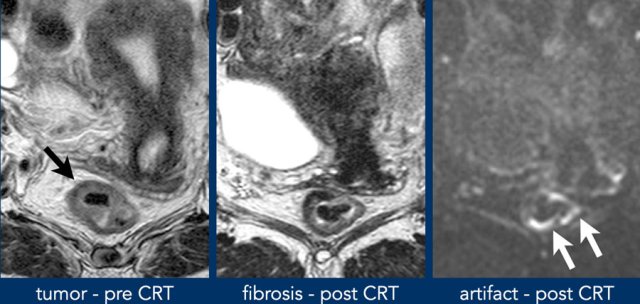

T2 dark through

Also called T2 black out, refers to the

markedly low signal observed on the ADC map in areas of dense fibrosis without

vital tumor.

This occurs in tissues with a very short T2-relaxation time (such

as collagen-rich fibrosis, calcified lesions and cortical bone) and will result

in a completely hypointense signal on the ADC map, but also on other series

including the DWI, T2-weighted and T1-weighted sequences.

should not be mistaken for restricted diffusion suspicious for tumor.

Example of shine through of high T2 signal on DWI from fluid in the rectal lumen.

The ADC map shows an example of T2 dark through with distintly low signal in the fibrotically changed rectal wall.

There is no corresponding high signal in the wall on DWI, indicating that there is no actual diffusion restriction.

Susceptibility artefacts

Abdominal DWI scans are often acquired using echo planar imaging (EPI), which allows fast image acquisition thereby minimizing the risk of motion artefacts.

The main downside of EPI-DWI is that it is highly prone to susceptibility effects, i.e. distortions or artificial pile up of MR signal caused by local field inhomogeneities, especially at higher field strengths.

In rectal DWI, these susceptibility effects mainly occur at the interface between soft tissue in the rectal wall or tumor and gas in the lumen.

While large artefacts will be easy to recognize as artefacts, more subtle ones projecting over the rectal wall may be erroneously interpreted as tumor signal.

Susceptibility artefacts in rectal DWI may be avoided by reducing the amount of gas in the rectal lumen or by using alternative methods of DWI acquisition, such as spin echo techniques, that are less prone to these susceptibility effects.

Images

This is a patient with tumor in the right anterolateral rectal wall. Post CRT there is fibrosis visible at the site of the former tumor bed from 9-12 o’clock.

The high signal on DWI is located on the contralateral side, outside the tumor bed and corresponds to susceptibility artefacts caused by gas in the rectal lumen. These artefacts should not be mistaken for high signal suspicious of tumor.